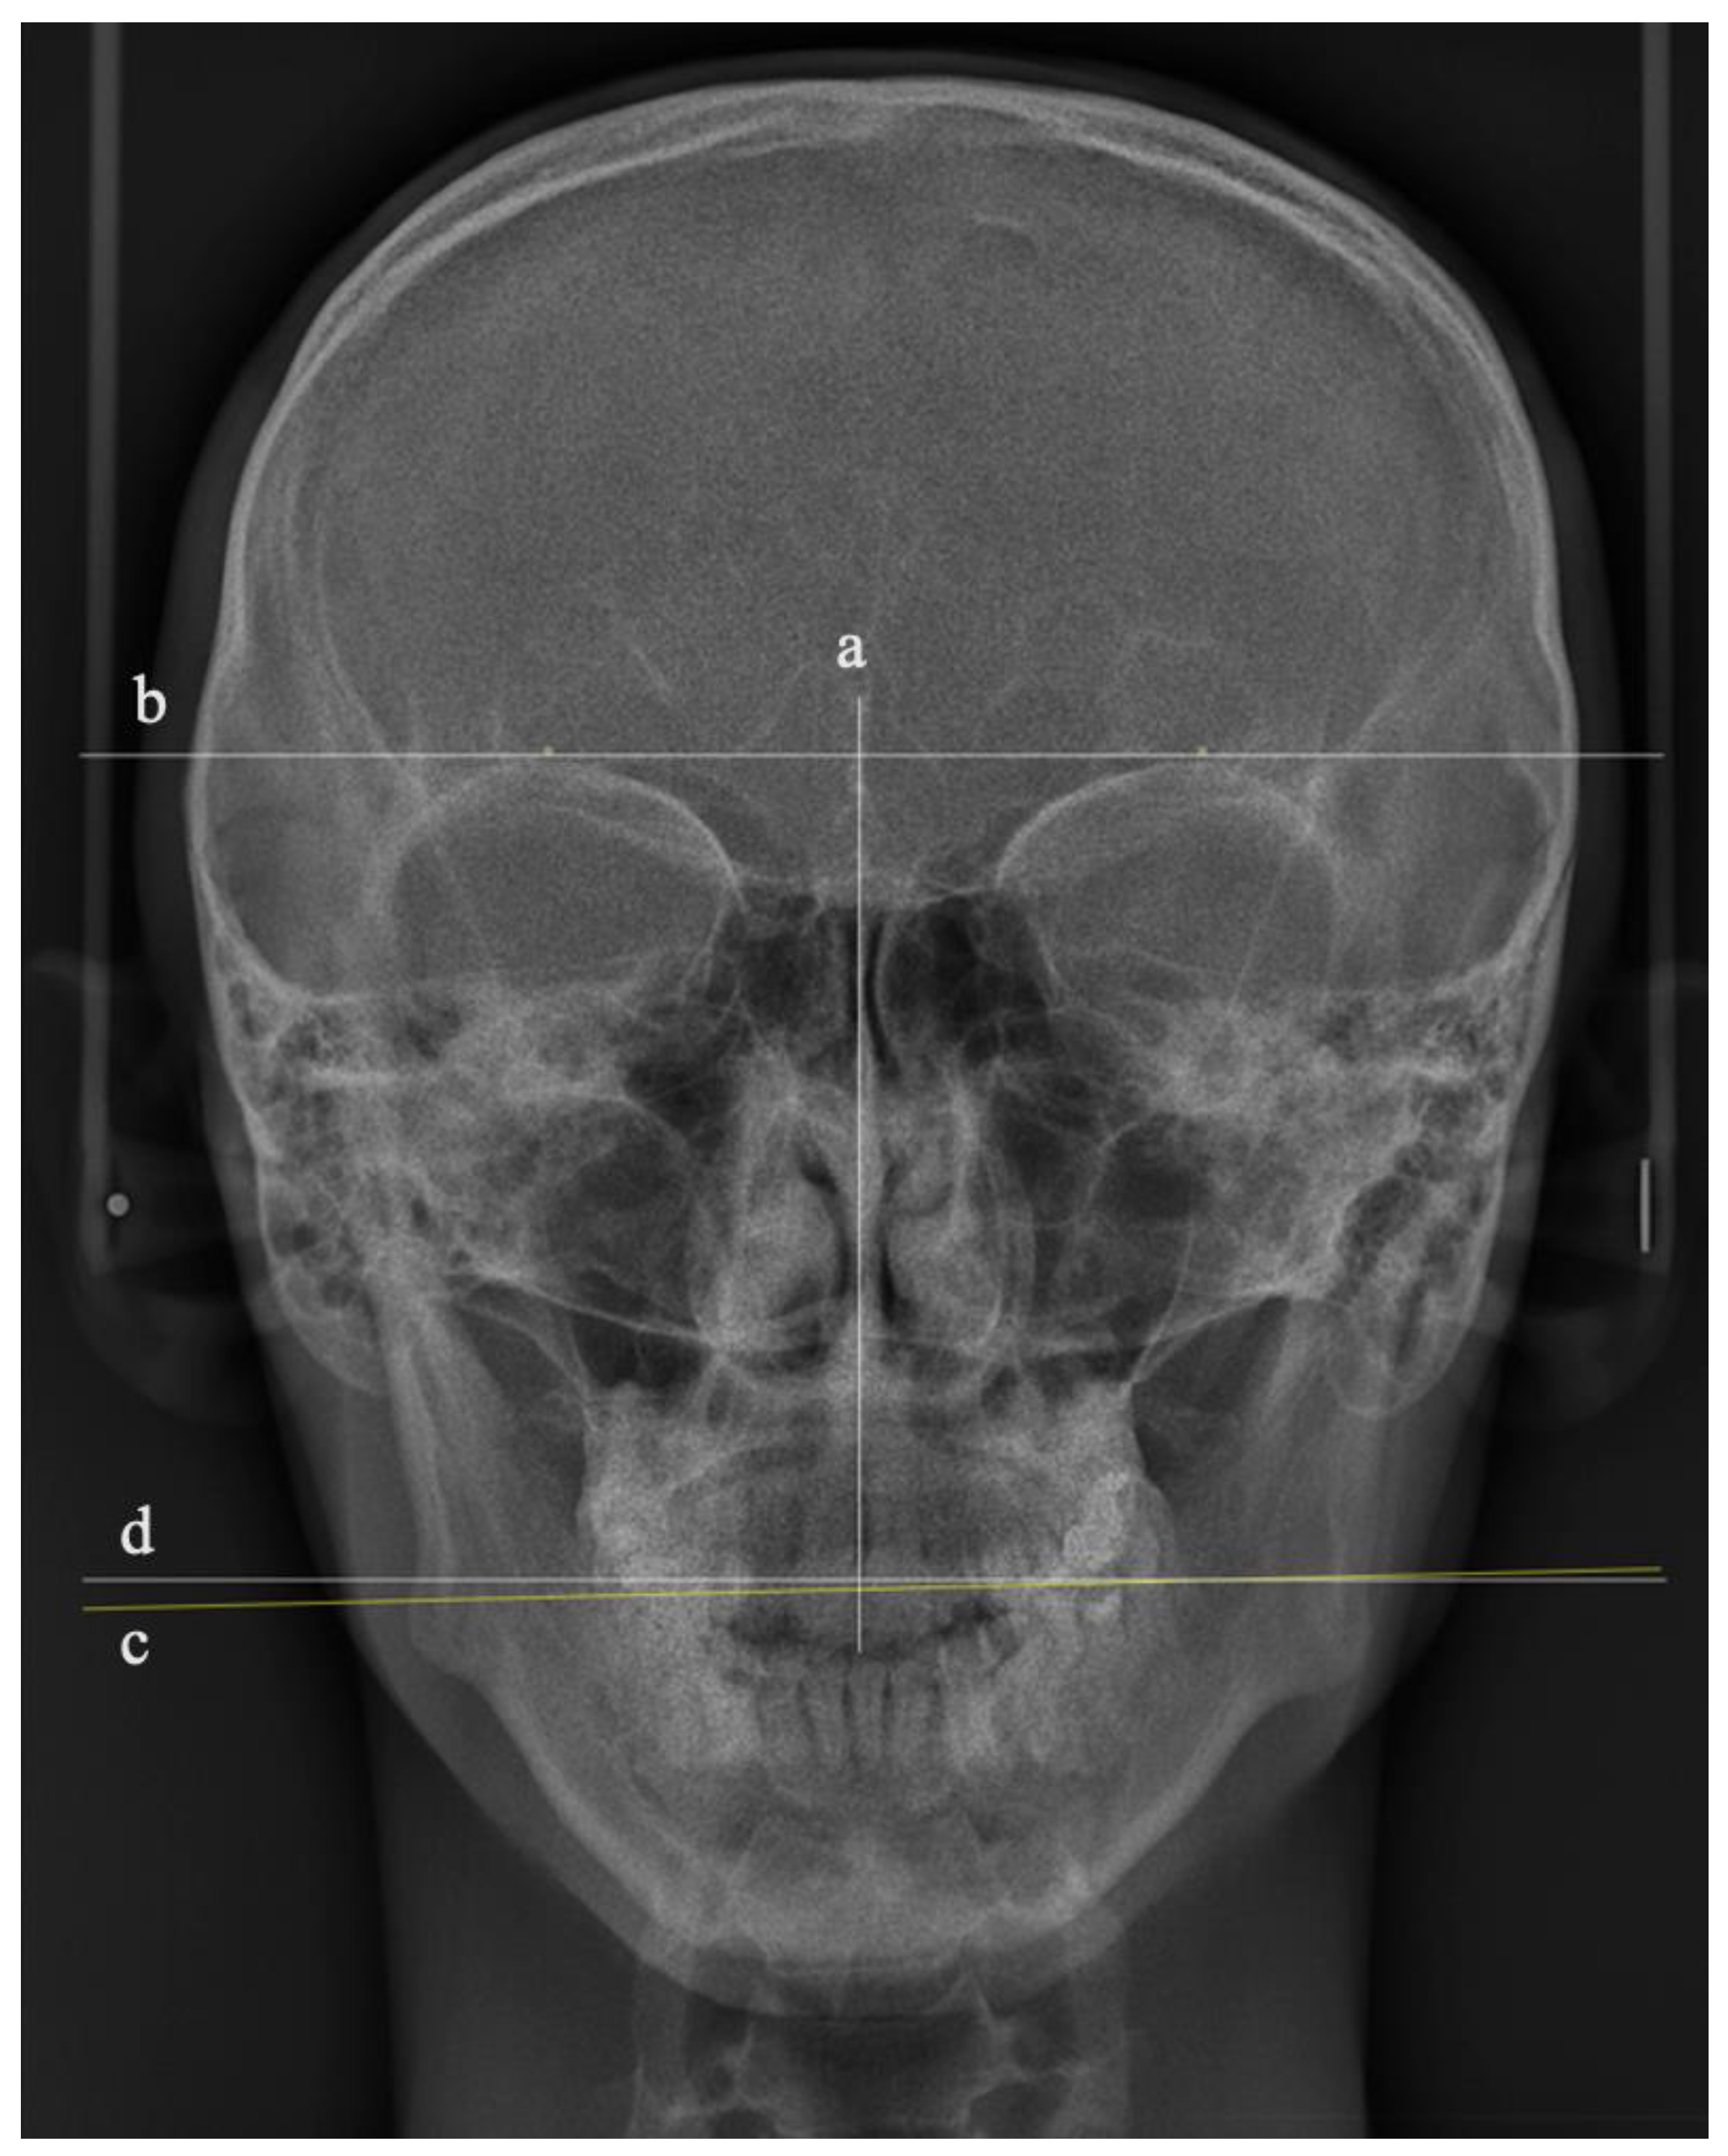

The manipulated 36 PA images were printed and traced by a single author. To measure the OC cephalometrically, three lines were drawn using a fine-tip pen (0.20 mm) (Sakura Pigman micron pen, Osaka, Japan), as shown in Figure 2:

Figure 2.

Illustration of the tracing lines of the PA cephalometric images: (a) vertical line representing the facial midline, (b) true horizontal line, (c) occlusal plane line, and (d) tangent parallel to the true horizontal line.

- A vertical line represents the facial midline, drawn from the crista galli to a point in the upper third of the nasal septum;

- A line represents the true horizontal plane, drawn as a tangent passing through the supra-orbital rims perpendicular to the vertical line;

- A line represents the occlusal plane (OP), drawn as a tangent to the most convex point of the buccal surfaces of the upper right and left first molars.

The degree of OC was represented by the angle bisecting these two horizontal lines [16]. Considering the distance between the two horizontal lines, an additional line parallel to the true horizontal tangent was drawn closer to the OP tangent to measure the OC angle (Figure 2). To assess the accuracy of the tracing, the angle of OC in degrees for all the traced 36 PA cephalometric images was remeasured by a second researcher. The set of 36 PA cephalometric images was arranged randomly to reduce systematic measurement errors among the participants, enhancing the study’s internal validity.